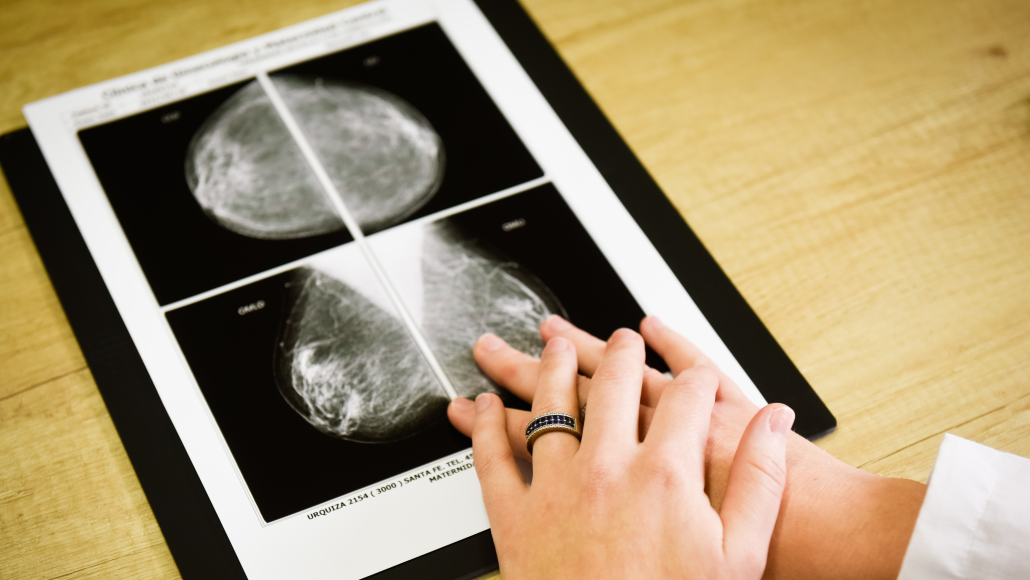

- Mastología y Cirugía

. Mastología y patología mamaria: detección precoz, diagnóstico y seguimiento.

. Oncoplastia y reconstrucción mamaria: integración de la cirugía oncológica con la estética y funcional.